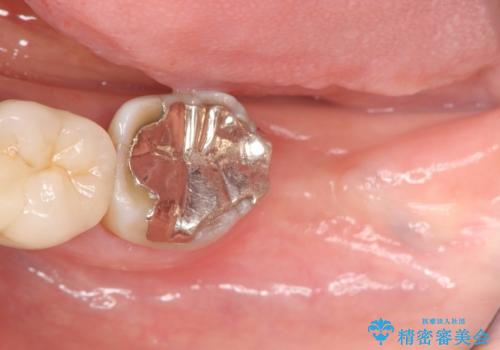

- 左下奥歯の咬合時疼痛を訴えて来院されました。

最後方臼歯周囲には大きな透過像が見られ、破折が強く疑われること抜歯が想定されることを理解していただき銀歯を除去したところ破折が認められたため抜歯を行いました。